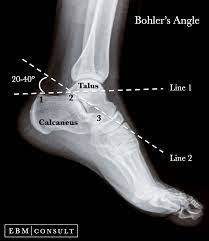

What is Bohler’s angle?